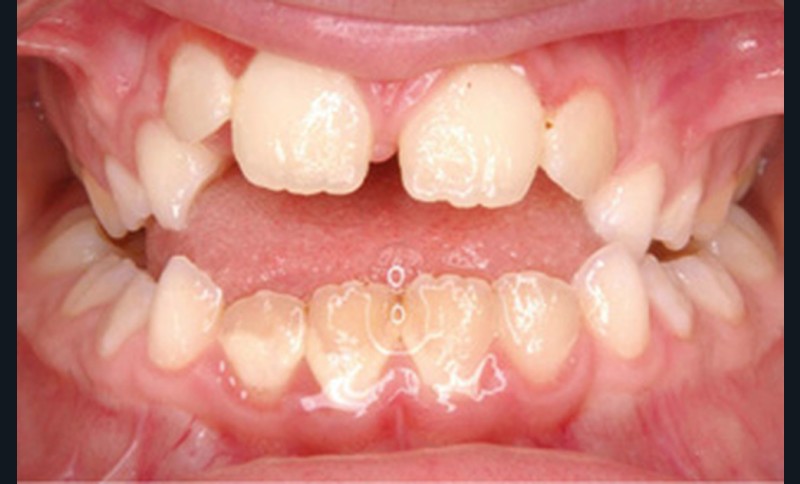

Cette patiente a été suivie dans le cadre d’un traitement interceptif alors qu’elle avait 9 ans. Elle présentait une endognathie maxillaire et une béance antérieure importante liées à des troubles fonctionnels évidents. En effet, l’examen clinique révélait une ventilation buccale exclusive, des ronflements nocturnes et une déglutition atypique. Nous avions noté à l’époque un manque de place pour l’évolution des dents définitives et un inversé d’articulé bilatéral. Les parents avaient rencontré un médecin ORL, mais avaient refusé une intervention visant à enlever les amygdales. Les deux canines maxillaires étaient incluses (fig. 1 à 6).

Quelques années plus tard, au moment de démarrer sa prise en charge orthodontique, la patiente présentait à nouveau une béance antérieure, un décalage des milieux incisifs de 2 mm et le problème transversal avait récidivé. Lors de l’examen clinique, elle présentait un inversé d’occlusion bilatéral postérieur et une ventilation buccale exclusive. À la suite du refus de réaliser l’amygdalectomie de façon précoce, elle ronflait toujours et sa déglutition ne s’était pas modifiée malgré des séances d’orthophonie (fig. 7 à 15).